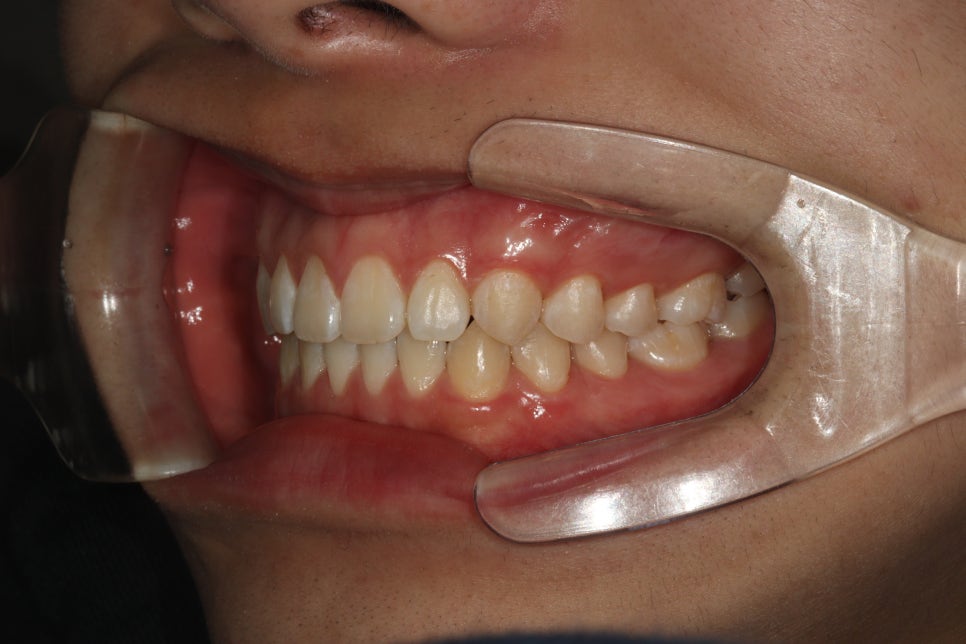

처음 내원하시고 약 4개월이 조금 넘은 기간의 변화입니다.

사실 여기서 끝내도 될 정도라고 하셨지만 제가 재제작한번 하자고 했어요

제 작품이라는 생각에 그냥 보내드릴 수 없죠 ㅎ

재제작을 통해 제 마음에 안들던 교합까지 형성해드리고, 치아배열도 마무리.

공간도 모두 없어지고 배열도 좋아졌습니다